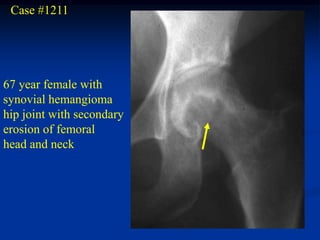

Case #1211

67 year female with

synovial hemangioma

hip joint with secondary

erosion of femoral

head and neck

Synovial biopsy showing numerous vascular spaces

Case #1211 67 yearfemale with synovial hemangioma hip joint with secondary erosion of femoral head and neck

• 358.

Synovial biopsy showingnumerous vascular spaces